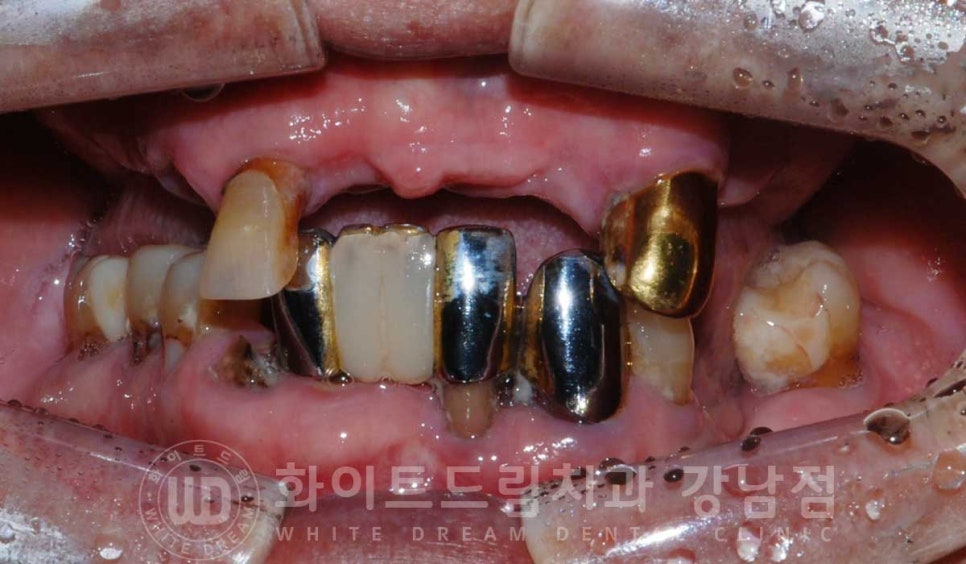

초기 구내 사진을 보면 상악 치아들은 대부분 없으신 상태로

남아있는 보철과 치아의 상태가 좋지 못하신 분입니다.

보철들도 20년 가까이 돼가면서 겉면에 치아색상으로 씌어놓은 도자기가 모두 벗겨져

내부 메탈이 겉으로 드러나있어 심미적으로도 굉장히 좋지 못한 상태였는데요.

환자분의 치료 전/후 사진입니다.

[동일 인물이며 동일 환경에서 촬영되었습니다.]